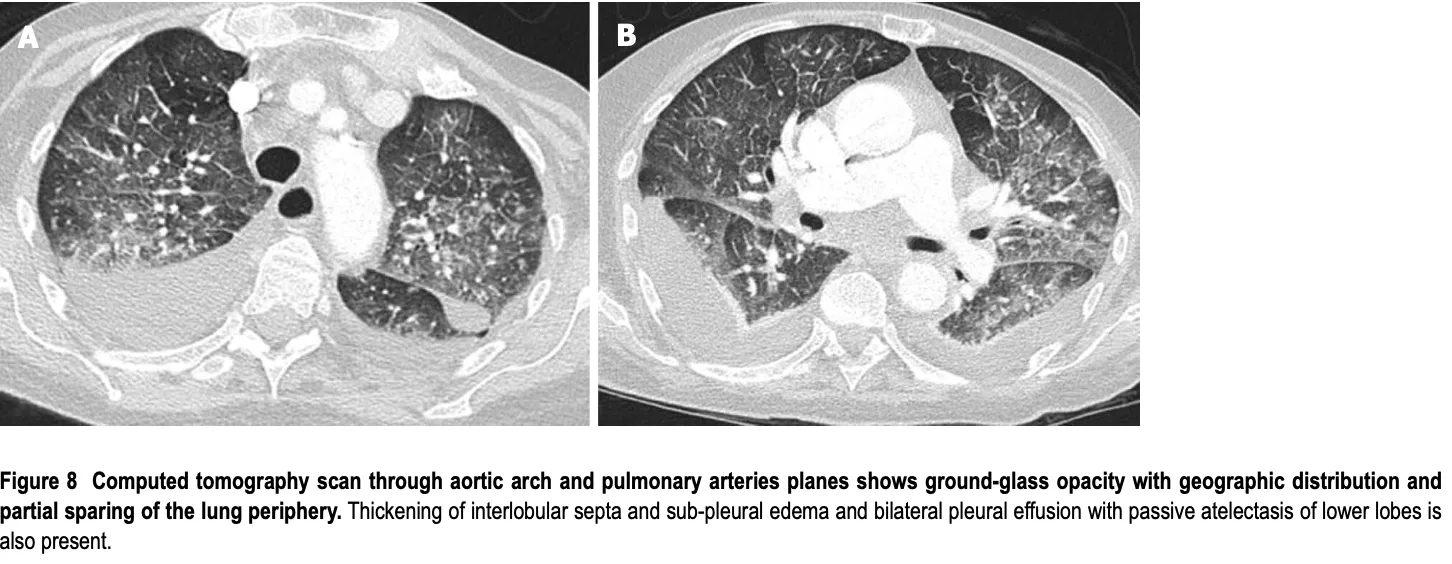

肺の中の水分の増加で, 本来黒く写る肺の内部が白っぽく写るようになり, 背中(下)側では, 肺の外側に貯まった水が胸郭に沿って拡がっています.

外来中に, 胸部CT画像を確認. 心臓の拡張があり, 両側に胸水が貯留していました. 既往に慢性心不全と慢性腎臓病があり, 急性増悪と判断. 利尿薬『アゾセミド』と『スピロノラクトン』を増量処方しました.